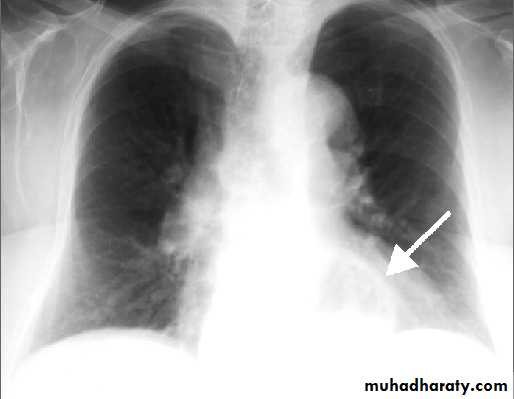

Thymoma.

A chest x-ray (A) reveals an unusual contour over the left hilum (arrows). That the hilum is not obscured (no silhouette sign) indicates that the mass must either be in front of or behind the hilum. A computed tomography scan (B) reveals a soft tissue mass (arrow) just to the left of the aorta. This is the most common location of a thymoma.